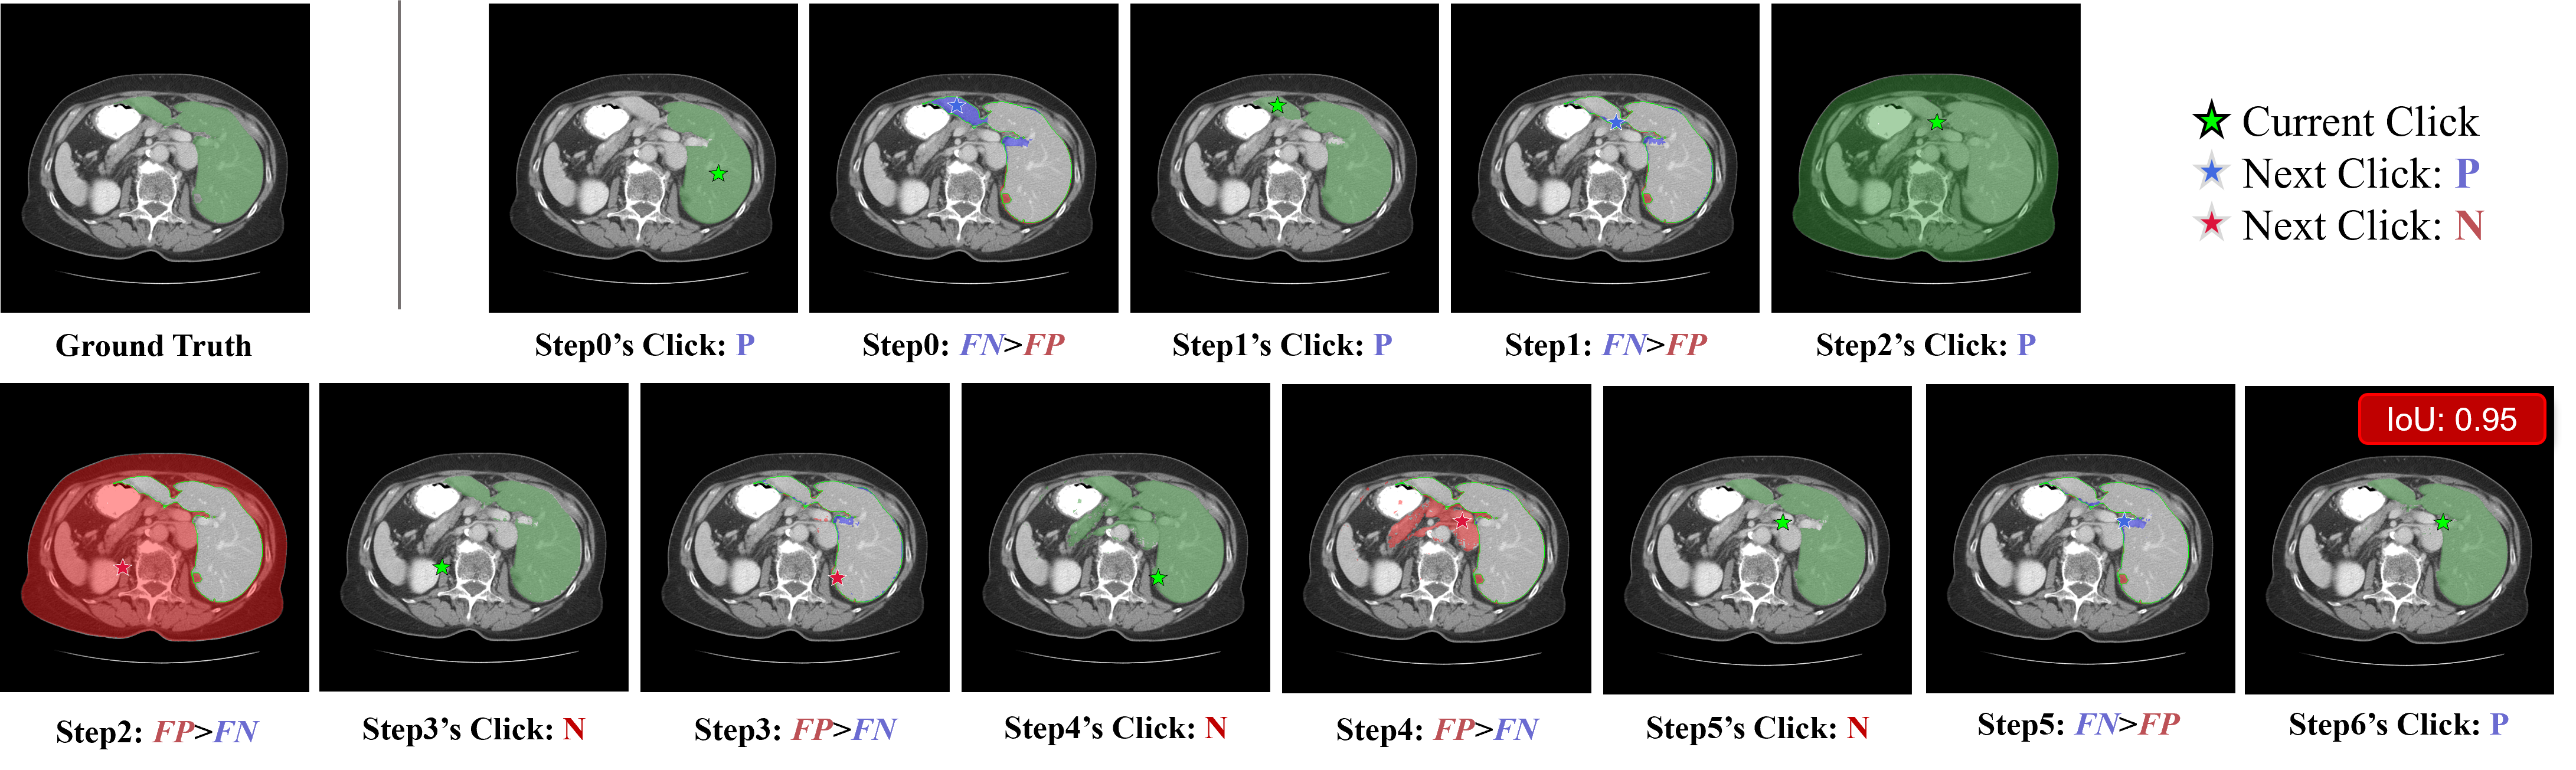

Refer to caption

Figure 3: Qualitative Analysis. We present the responses and segmentation outputs on a reasoning–segmentation example. Existing MLLMs exhibit incorrect reasoning and low-quality segmentation, highlighting their misaligned fine-grained vision–language understanding. In contrast, IBISAgent delivers substantially improved reasoning quality and segmentation performance.

Qualitative Analysis. As shown in Fig. 3, we present qualitative results that further demonstrate the merits of IBISAgent. For a case requiring reasoning to identify a liver tumor, the powerful closed-source GPT-4o [hurst2024gpt] outputs seemingly correct textual reasoning but produces an incorrect localization bounding box. This indicates that the model fails to align textual reasoning with visual features—it may be hallucinating plausible answers rather than truly understanding the medical image, ultimately leading to incorrect localization. MedPLIB [huang2025towards] provides coarse localization that roughly captures the lesion region but suffers from false-positive predictions. Moreover, its language output is highly constrained—when performing segmentation, the model rigidly outputs only the token “<SEG>”, losing the rich language generation capability originally inherent to large language models. UniBiomed [wu2025unibiomed] produces incorrect textual reasoning and responses, describing objects that do not exist in the image and generating low-quality segmentation masks. This observation reinforces our motivation: current methods that rely on implicit “<SEG>” tokens for segmentation disrupt the MLLM’s native text output space, compromising both its language capability and semantic generalization. Moreover, these approaches exhibit fundamentally limited pixel-level visual reasoning, preventing the model from truly understanding fine-grained visual features. In contrast, IBISAgent not only generates correct and coherent textual reasoning but also adaptively produces high-quality masks through step-by-step, precise pixel grounding. This capability arises from our design that decouples reasoning from segmentation, thereby preserving the MLLM’s inherent language reasoning ability while simultaneously enabling adaptive, multi-round refinement.